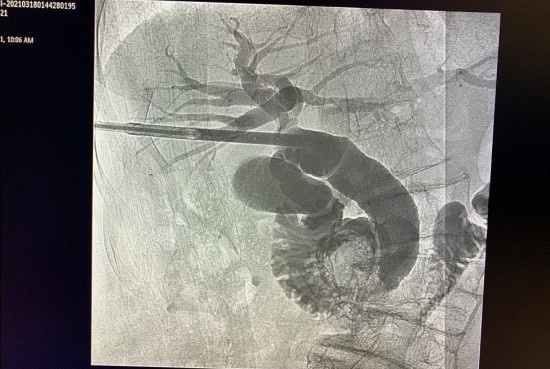

Hình ảnh tán sỏi mật dưới da cho bệnh nhân. Ảnh: BVCC.

Với kỹ thuật này, phẫu thuật viên sẽ chọc một đường duy nhất dài khoảng 3-5 mm từ ngoài cơ thể xuyên qua da ngoài thành bụng vào đường mật trong gan. Qua can thiệp, các vị trí có sỏi sẽ được tán nhỏ, hút ra ngoài và bơm rửa lấy hết cặn sỏi.